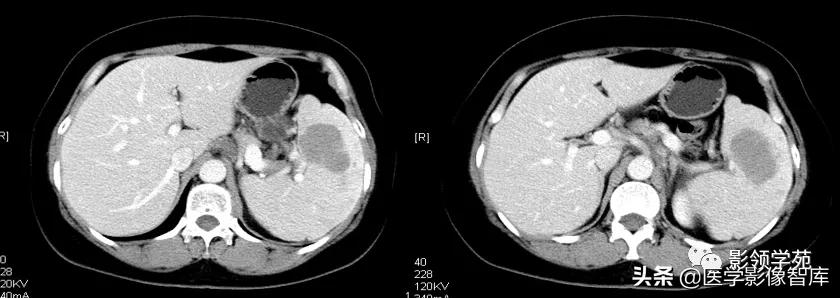

2.全身性淋巴瘤脾浸润:1)脾肿大,弥漫性脾浸润,呈小结节状低密度灶,密度不均匀,结节大小在1cm以下。2)增强扫描脾实质低密度轻度强化结节。肝脏多同时受累。